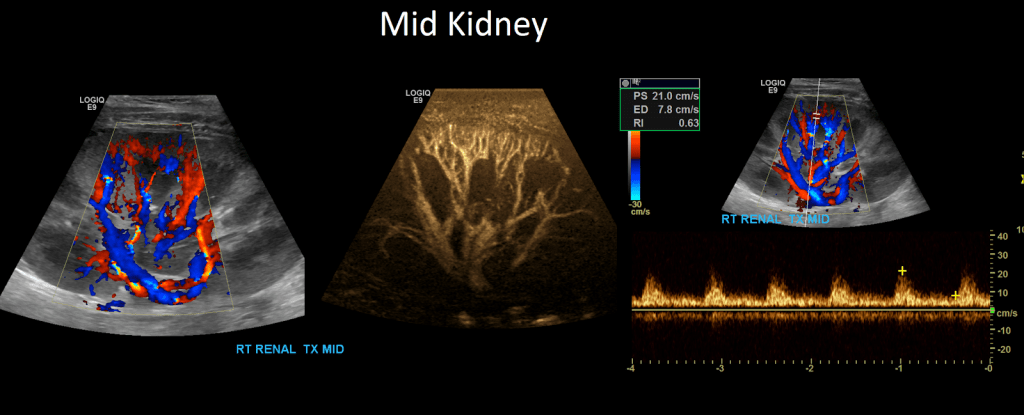

Once that is complete move on to Doppler the arcuate/segmental arteries (your institution may require one or the other or both). Doppler these arteries in the superior, mid and inferior pole of the kidney. Do not use angle correction.

Measure the peak systolic and end diastolic velocity. Resistive Index is normally between 0.50 and 0.70. The waveform should be a low resistance waveform with forward flow throughout the cardiac cycle. Take Doppler samples at the anastomosis/proximal section (pay close attention here look for aliasing to detect anastomotic stenosis), the mid and distal portions as well. If there’s any aliasing along the vessel take spectral Doppler samples there too.